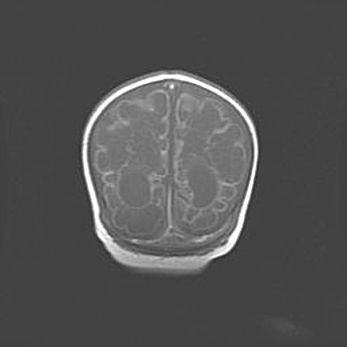

Множественные кисты обоих полушарий головного мозга, наибольшая из них в правой затылочной области. Ассиметричная атрофическая гидроцефалия.

Возраст: 7 месяцев

Вес: 5660 г

Пол: мужской

Окружность головы: 41,5 см

Срок гестации: 28-29 недель

Кисты головного мозга развиваются в результате многоочаговых некрозов вещества мозга и возникают вследствие перенесенной перинатальной инфекции, менингитов, энцефалитов, асфиксии, родовой травмы, расстройств мозгового кровообращения различного генеза. Образованию кист в веществе головного мозга плодов и новорожденных способствуют такие факторы, как высокое содержание в нем воды, недостаточная (или отсутствие) миелинизация и слабая астроглиальная реакция на повреждение.

Кисты могут сочетаться с гидроцефалией и другими поражениями головного мозга.